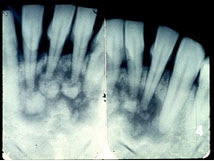

图为牙骨质瘤的X线表现,关于此病描述不正确的是()

A、来源于牙胚的牙囊或牙周膜

B、肿瘤紧贴牙根部,可单发或多发

C、牙髓活力测试是阴性的

D、生长缓慢,一般无自觉症状

E、X线显示根尖周围有不透光的阴影

C